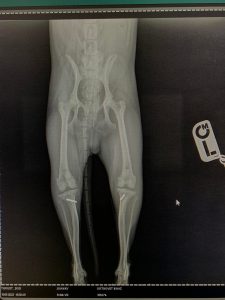

- Liječenje prijeloma kostiju, uključujući intraartikularne frakture

- Liječenje luksacije patele(Luxatio Patellae) Trohleoplastika i TTT(eng. Tibial Tuberosity Transposition)

- Liječenje rupture prednjeg križnog ligamenta koljena TPLO (eng. Tibial Plateau Leveling Osteotomy)